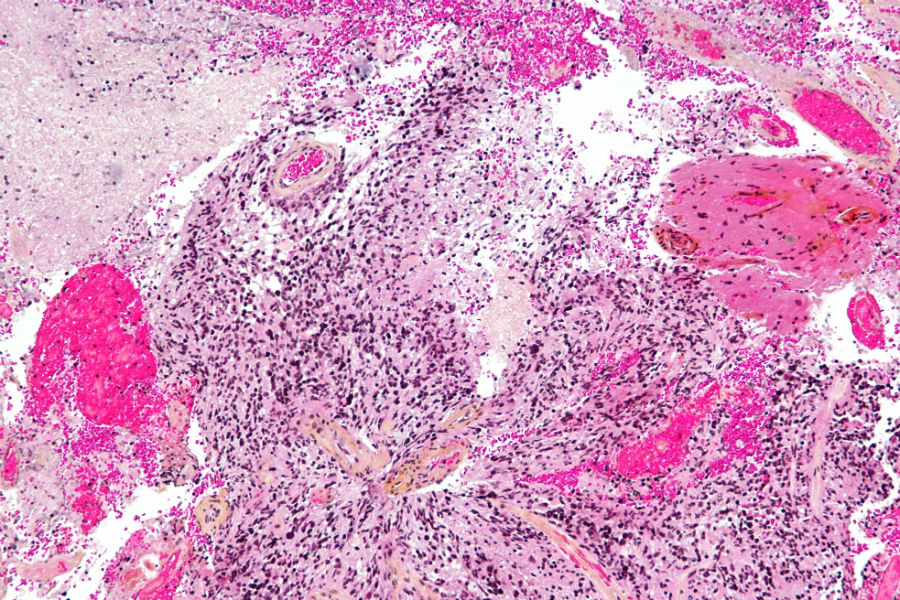

Снимок глиобластомыФото: wellcomeimages.com